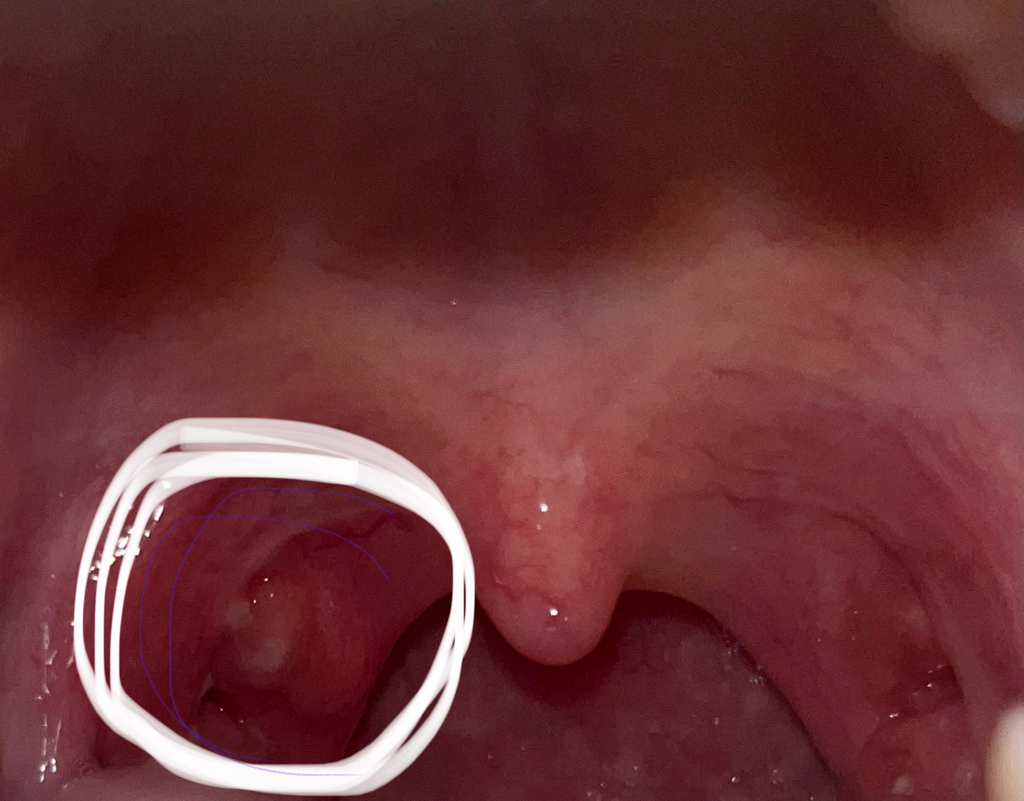

편도암인가요…………………………

오늘 편도염때문에 병원 갔다왔는데 동그라미 친 부분이 갑자기 커진거같아요.. 병원에선 의사선생님이 별 말 안하시긴 했는데 편도얌 자주 앓고 나서부터 저 부분이 단순히 부어오른건가요..?

• 안녕하세요. 서민석 의사입니다.

편도염을 않을때 편도 주변으로 농양이 생기기도 합니다. 그럼 주변이 붓고 증상도 오래갑니다. 편도암은 아닌것 같으니 염증치료 먼저 잘 받으시기 바랍니다.